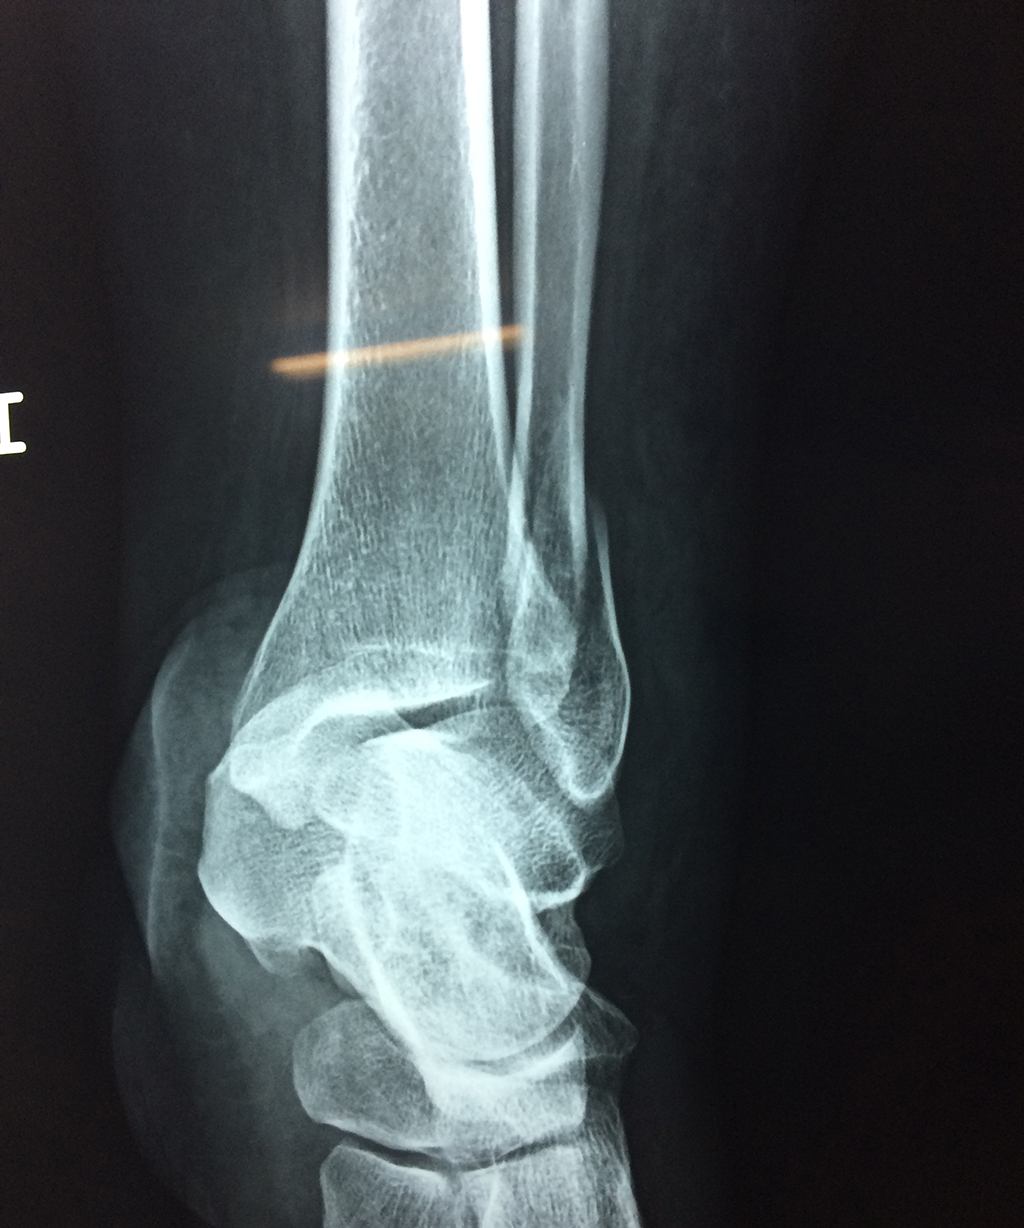

Una fractura de tobillo es la rotura de uno o más de los huesos del tobillo. Estas fracturas pueden ser:

Algunas fracturas de tobillo pueden requerir cirugía si:

- Los extremos de los huesos están desalineados entre sí (desplazados).

- La fractura se extiende hasta la articulación del tobillo (fractura intra-articular).

- Los tendones o ligamentos (tejidos que sujetan los músculos y los huesos entre sí) están rotos.

Cuando se necesita cirugía, es probable que esta implique el uso de clavijas de metal, tornillos o placas para sostener los huesos en su lugar mientras la fractura se consolida. Los elementos de soporte pueden ser temporales o permanentes.